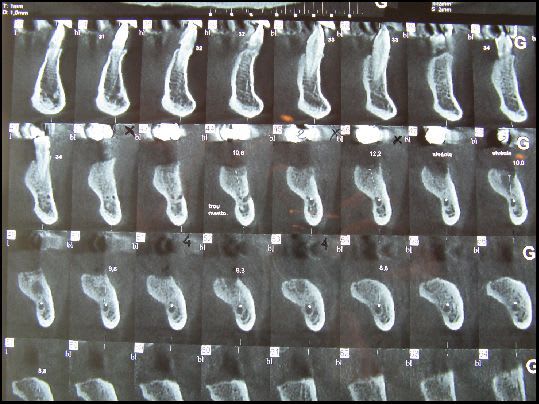

21 jours post-op

Pp